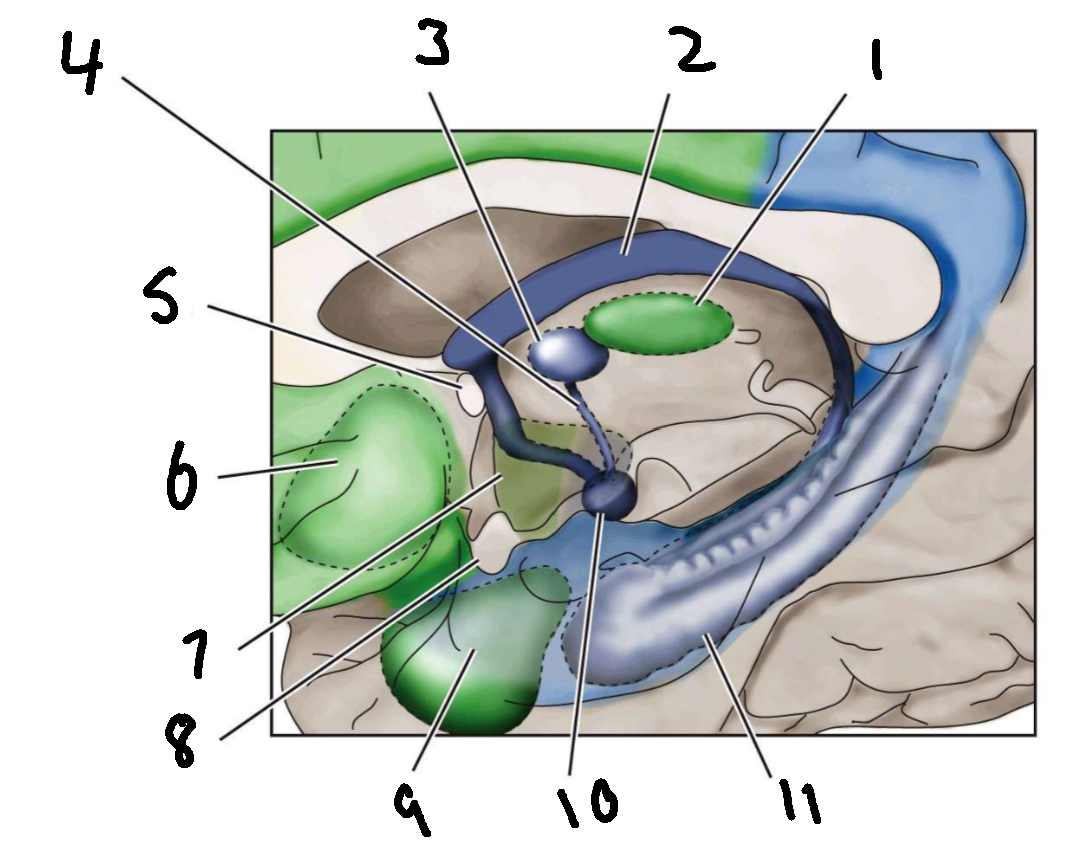

What is 1?

mediodorsal nucleus of the thalamus

What is 2?

fornix

What is 3?

anterior nucleus of the thalamus

What is 4?

mammillothalamic tract

What is 5?

anterior commissure

What is 6?

ventral basal ganglia

What is 7?

hypothalamus

What is 8?

optic chiasm

What is 9?

amygdala

What is 10?

mammillary body

What is 11?

hippocampus